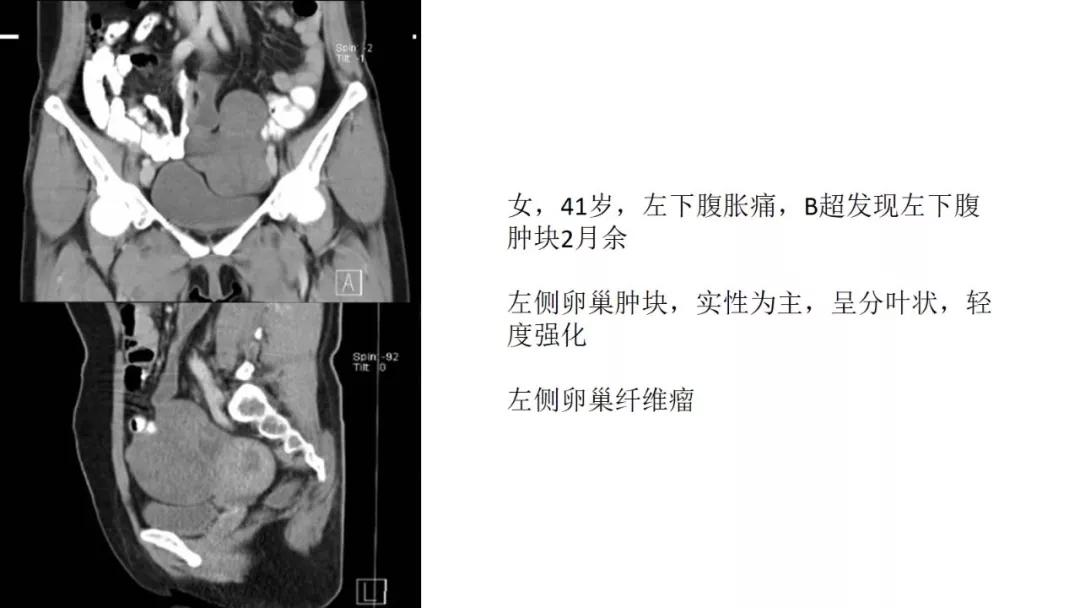

女,39 岁,体检发现盆腔肿块1月余

CA125:51U/ml

病理:左侧卵巢卵泡膜-纤维瘤